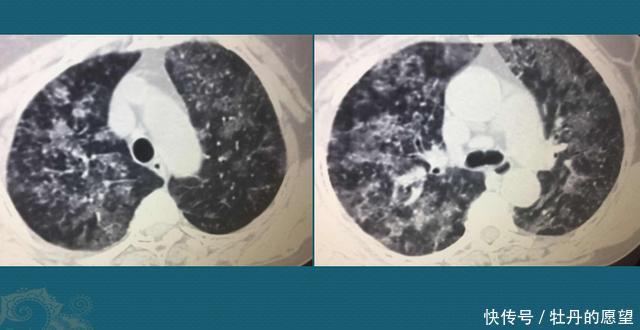

重磅!美国首例新冠病毒肺炎治疗康复全过程 | N

1080x863 - 67KB - JPEG